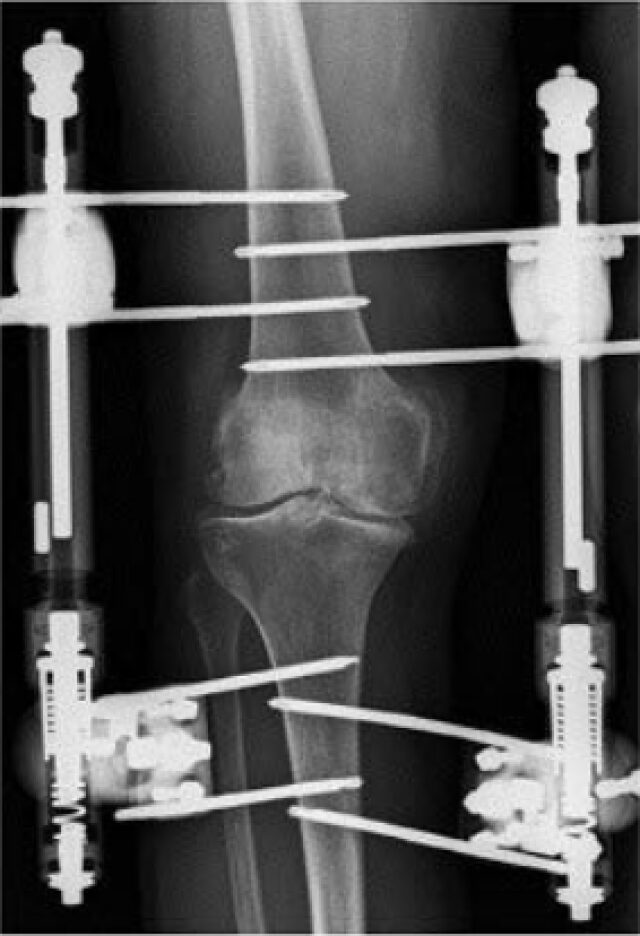

Behandeling met kniedistractie kan bijwerkingen en complicaties hebben.

De pennen die in het bot worden geplaatst om het distractieframe vast te maken, kunnen leiden tot roodheid en zwelling van de huid rondom de pennen. Dit kan pijnlijk zijn, maar het is goed te behandelen met antibiotica.

Tijdens de kniedistractie kan de knie gedurende 6 weken niet bewegen, dit kan leiden tot stijfheid van het gewricht. In overleg met de orthopedisch chirurg kan eventueel fysiotherapie worden gestart om de beweeglijkheid te herstellen.